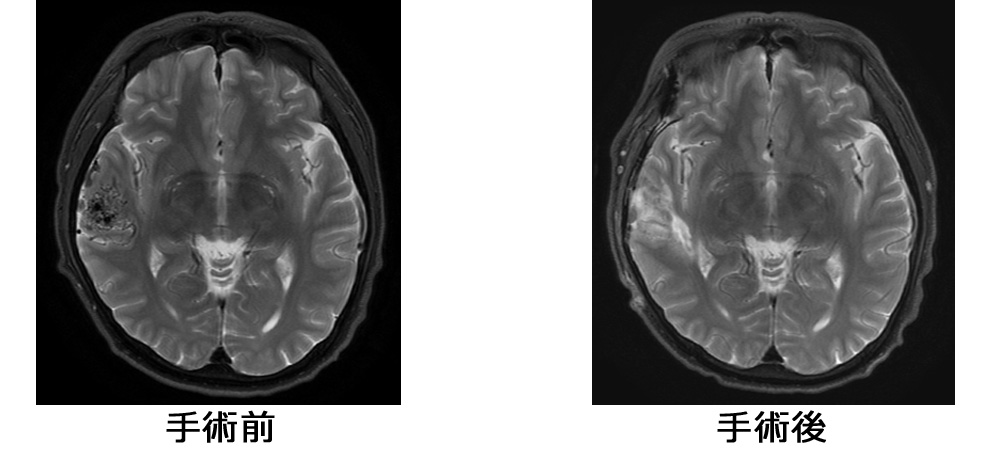

「手術後」ではナイダスが消失していることがわかります。